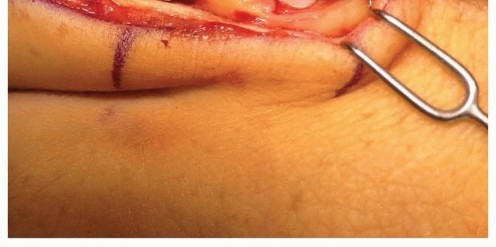

FIG 6 • Dorsal approach to the MP joint of an index finger. Extensor tendon beneath top retractor. Capsule grabbed by pickup forceps. Articular cartilage seen deep to capsule.